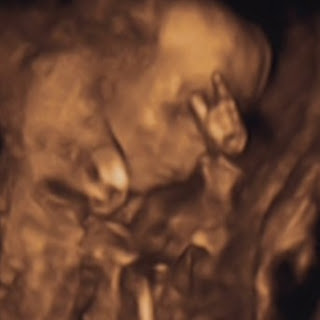

Keresztes Marcell jelenleg 17 cm és makkegészséges! Mindene a helyén van, az apját természetesen a kukaca kötötte le leginkább! :D :P

Kis mozgékony babánkról alig lehetett készíteni egy értelmes fényképet, mert hol a kis seggét mutogotta, hol törökülésbe vágta magát, hol fejen állt! :D

Azért egy kép mégis sikerült, holnap meg is mutatom Nektek! :)